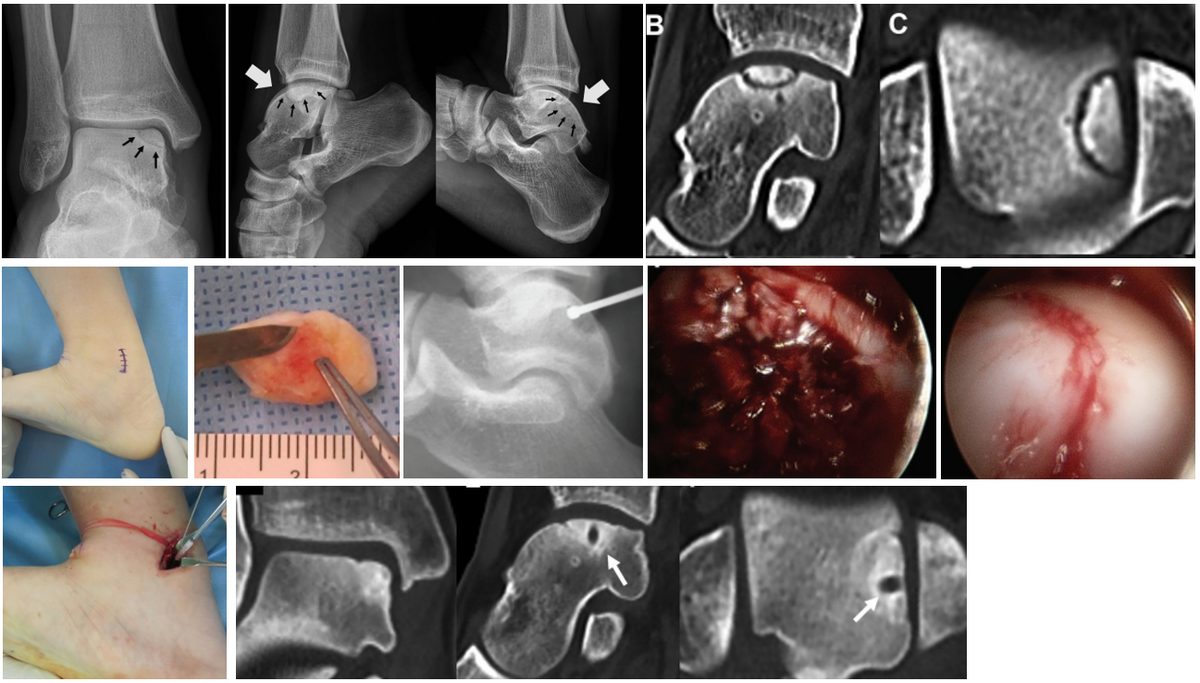

Рис. 2. Рентгенологическая классификация остеохондральных повреждений таранной кости по Berndt и Harty (1959)

Диагностика

Стандартная рентгенография

Первый метод визуализации. Обязательные проекции:

- Передне-задняя (AP) — в положении стоя, стопа перпендикулярно кассете

- Боковая — в положении стоя

- Mortise view (передне-задняя с внутренней ротацией голени на 15-20°) — позволяет визуализировать купол таранной кости без наложения малоберцовой кости; наиболее информативна для ОХП

На что обращать внимание: участки просветления (радиолюценции) или склероза на куполе таранной кости, свободные внутрисуставные тела, оценка суставной щели, ось конечности.

Чувствительность рентгенографии для ОХП невысока — до 43% повреждений не выявляются (Hepple, 1999). Рентгенография отрицательна практически во всех случаях при стадиях Berndt-Harty I и большинстве случаев стадии II. Основная роль рентгенографии — исключение переломов, оценка артроза, первичная оценка видимых ОХП.

КТ (мультиспиральная компьютерная томография)

Показания:

- Предоперационное планирование — прецизионная оценка размера и глубины костного дефекта

- Выявление субхондральных кист (размер, количество, расположение)

- Оценка состояния субхондральной пластинки — наличие фрагментации, склероза

- Оценка консолидации после остеотомии (послеоперационный контроль)

Преимущества КТ перед МРТ: более точная оценка костного компонента, лучшее пространственное разрешение для кист и костных дефектов, возможность 3D-реконструкции.

Ограничения: минимальная информация о хрящевом компоненте; ионизирующее излучение.

КЛКТ с артрографией (Cone Beam CT arthrography)

Перспективный метод, комбинирующий высокое пространственное разрешение КЛКТ с контрастированием суставного пространства:

- Позволяет визуализировать тонкий хрящ (1-1.7 мм) таранной кости значительно лучше, чем стандартная МРТ

- Выявляет нарушения целостности хрящевой поверхности: трещины, фибрилляцию, лоскутные разрывы

- Показана при расхождении клинических данных и результатов МРТ

- Доза облучения ниже, чем при МСКТ

- По данным Defined CT (2018), КЛКТ-артрография превосходит МРТ 1.5Т в точности стадирования хрящевых повреждений